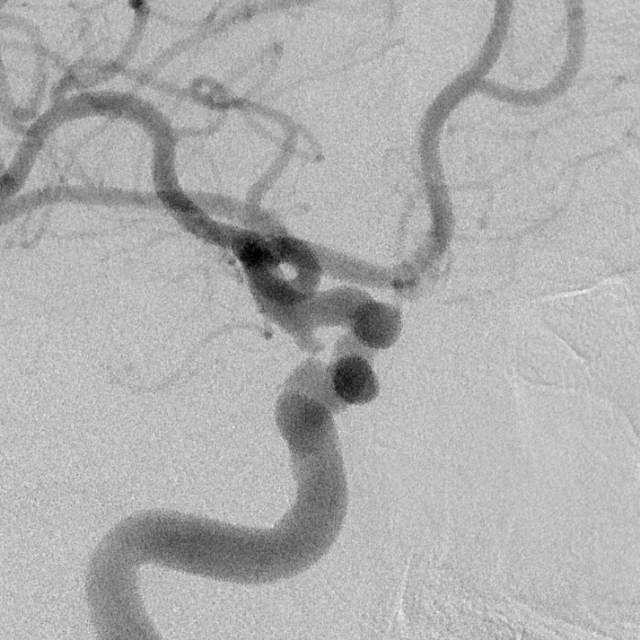

病情变化:中年男性患者,由于头晕查体发现后交通动脉瘤,第一次造影可见形态尚规则,患者及家属经过反反复复的思想斗争,决定采用外科干预。3天后,术中发现动脉瘤的形态已经出现改变,瘤囊的远端出现子瘤。

患者选择:一般而言,这种进展性形态变化伴有子瘤的病变容易出现破裂出血,患者的本次决定真是不失时机的明智之选。

病例启示:颅内动脉瘤的形态存在不断改变的可能,这是趋向破裂的一种危险现象。